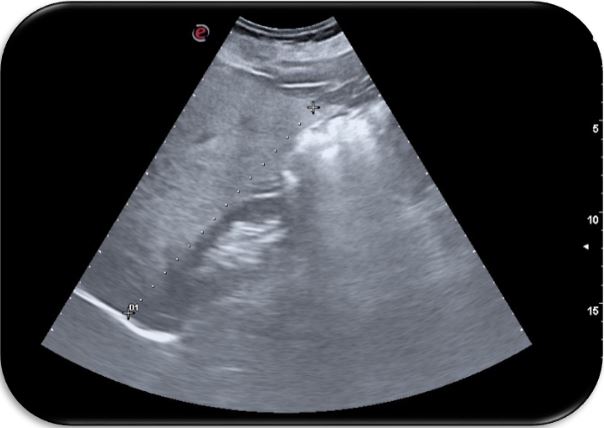

De esta forma, comenzamos a utilizar la ecografía no solo como herramienta diagnóstica, sino también como instrumento de concienciación visual. Así, mostramos en directo al paciente sus placas de ateroma en carótidas o femorales, o la hiperecogenicidad hepática fruto de su esteatosis. Al ver su daño, muchos cambian de actitud. Frases como «¿esto está dentro de mí, doctora?» se repiten, y suelen ir seguidas de decisiones reales. Ese momento es mágico. La negación se rompe. La conciencia se enciende. El cambio empieza. Tras ver sus imágenes, pacientes que no tomaban tratamiento empezaron a hacerlo. Fumadores empedernidos pidieron ayuda. Personas que decían «ya adelgazaré» empezaron a perder peso. Todo, porque lo vieron.